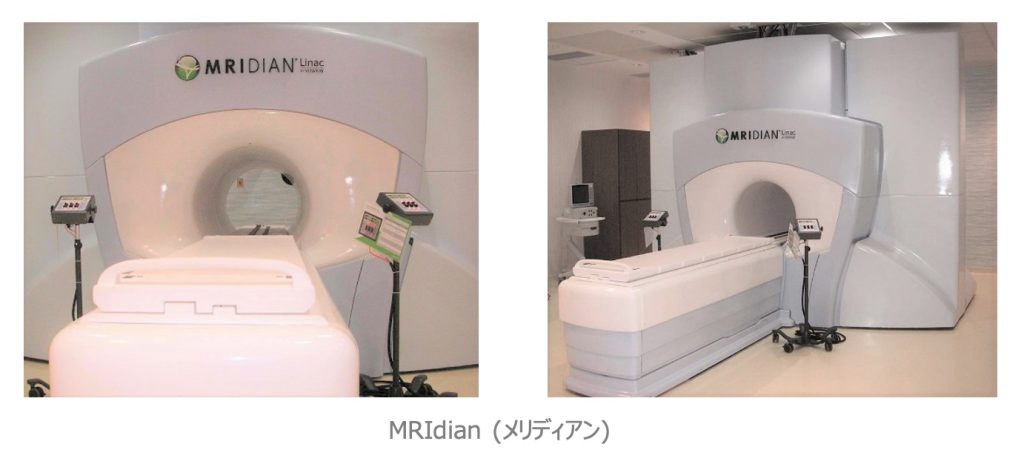

●MR画像誘導放射線治療システム MRIdian Linac

《メリディアン リニアック:VIEWRAY社》

6MV-X線リニアック装置と0.35テスラの低磁場MR装置を融合させたシステムで、MR画像を位置照合に使用して正確に照射する“MR画像誘導放射線治療“を行う事が出来ます。更に、腫瘍や周囲臓器を随時観察する事ができ、状況に応じて治療計画の見直しを行い、最適な照射に切り替える”On-Line Adaptive RT”が可能です。また、照射中にMR画像を撮像しながら呼吸により移動する腫瘍に対して、正確に放射線を照射する“Real Time Gating“の機能が備わっています。当センターに2022年度導入された装置です。